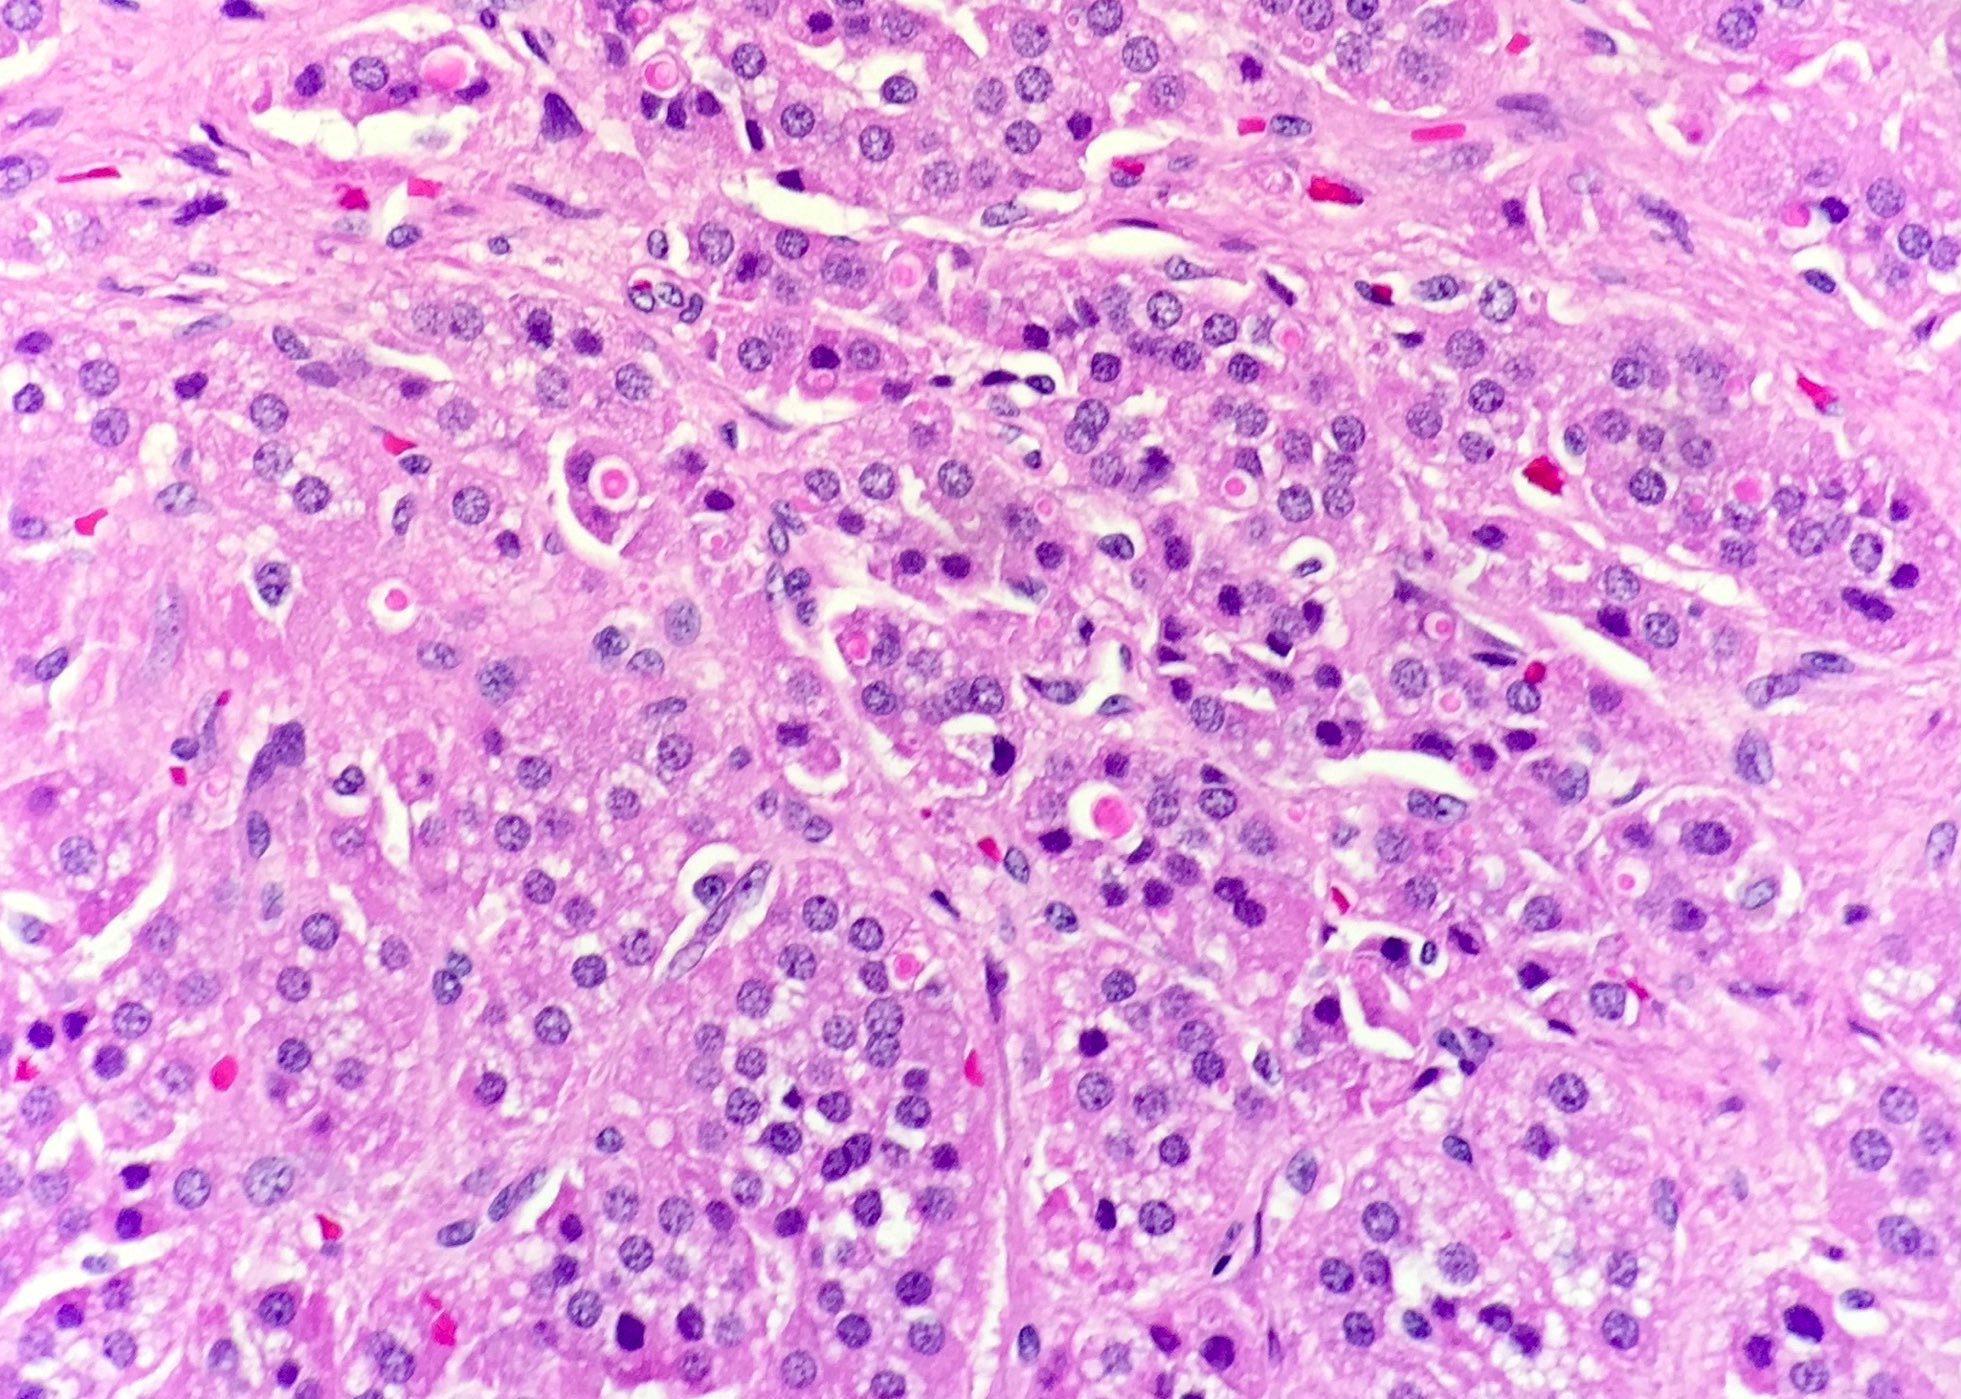

Microscopic (histologic) description

- In comparison to surrounding adrenal gland, adenoma cells are larger with different cytoplasm, increased variation in nuclear size

- Distinct cell borders, cells have abundant foamy cytoplasm reminiscent of zona fasciculata

- Balloon cells: clusters of cells with enlarged lipid-rich cytoplasm (seen in Cushing syndrome)

- Histologic variants: oncocytic, myxoid

Microscopic (histologic) images

Contributed by Xiaoyin "Sara" Jiang, M.D., Debra Zynger, M.D., @Andrew_Fltv on Twitter and @SueEPig on Twitter